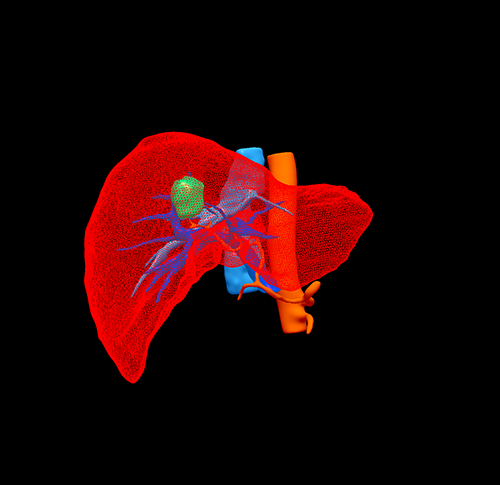

S58 肝癌--腹腔镜S58部分切除